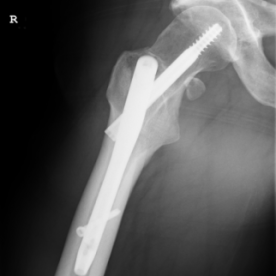

Röntgenbilder